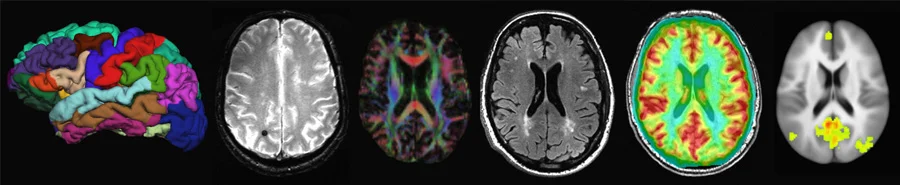

La prova definitiva dell’efficacia delle tecniche psicoterapeutiche è venuta però da pochi anni, con l’applicazione delle immagini di risonanza magnetica.

Gli studi sperimentali si sono avvalsi delle attuali metodiche di visualizzazione in vivo del cervello, che sono la tomografia ad emissione di positroni (PET) e la risonanza magnetica funzionale (fMRI). I primi risalgono a non più di una decina d’anni fa. Sono stati esaminati gruppi diversi di pazienti, affetti dal disturbo ossessivo-compulsivo, dalla fobia specifica o sociale, ed altri con disturbi depressivi maggiori o schizofrenici.